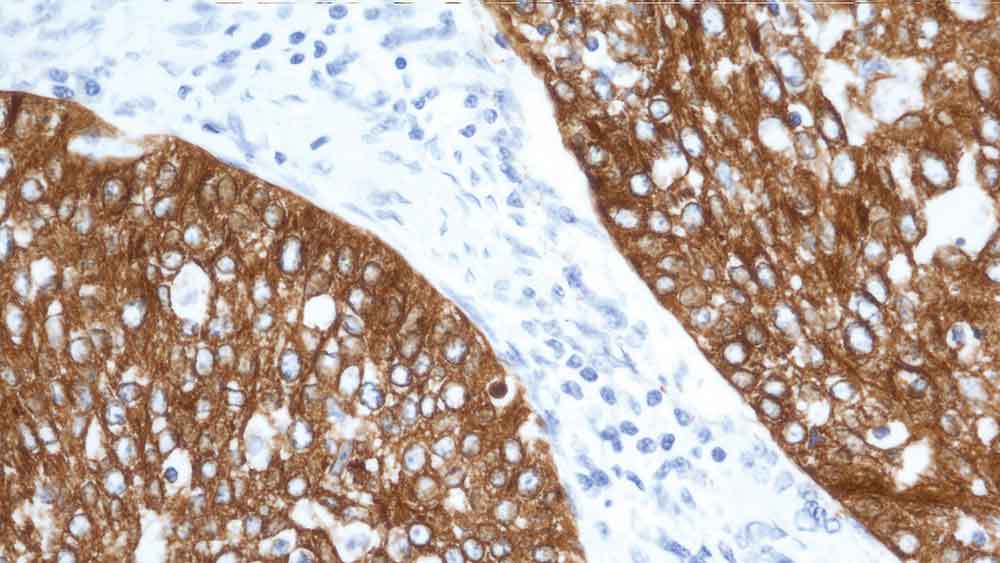

Human rectal adenocarcinoma: immunohistochemical staining for Cytokeratin 19. Note: cytoplasmic staining of malignant epithelial cells. Cytokeratin 19: clone b170

La plus petite cytokératine humaine des filaments intermédiaires (40 kD) est la cytokératine 19, dont on a observé l'expression dans un grand nombre de types cellulaires épithéliaux, y compris dans de nombreux épithéliums canalaires et glandulaires.

Le NCL-CK19 produit un motif de marquage hétérogène complexe dans les épithéliums squameux non kératinisants et dans les follicules pileux, dans lequel on observe un marquage intense de la couche basale.